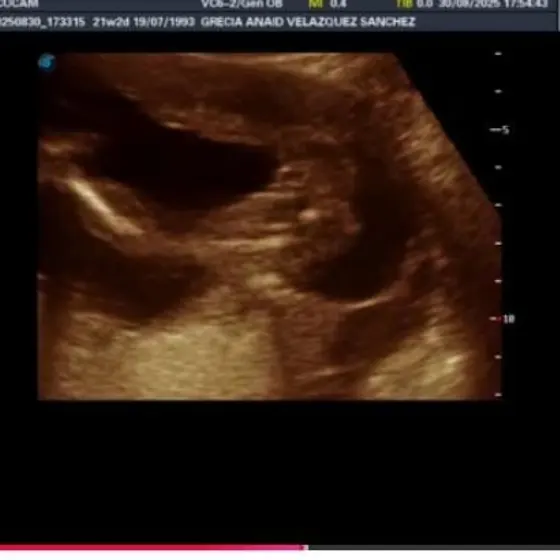

Es una niñaaa🩷🦆💕✨ La bebé que está en proceso será una niña tal vez se llame Melanie Annushka 🤭🩷💕✨ ahora si tendremos que hacer compras forzosas de ropa y accesorios de bebé de color rosa😍🤭🩷 y muchos moños y diademas y vestidos jaja #girl#baby#babygirl#kids#pregnant#embarazo#mom#minnie#daugther#family

Es una niñaaa🩷🦆💕✨ La bebé que está en proceso será una niña tal vez se llame Melanie Annushka 🤭🩷💕✨ ahora si tendremos que hacer compras forzosas de ropa y accesorios de bebé de color rosa😍🤭🩷 y muchos moños y diademas y vestidos jaja #girl #baby #babygirl #kids #pregnant #embarazo #mom #minnie #daugther #family